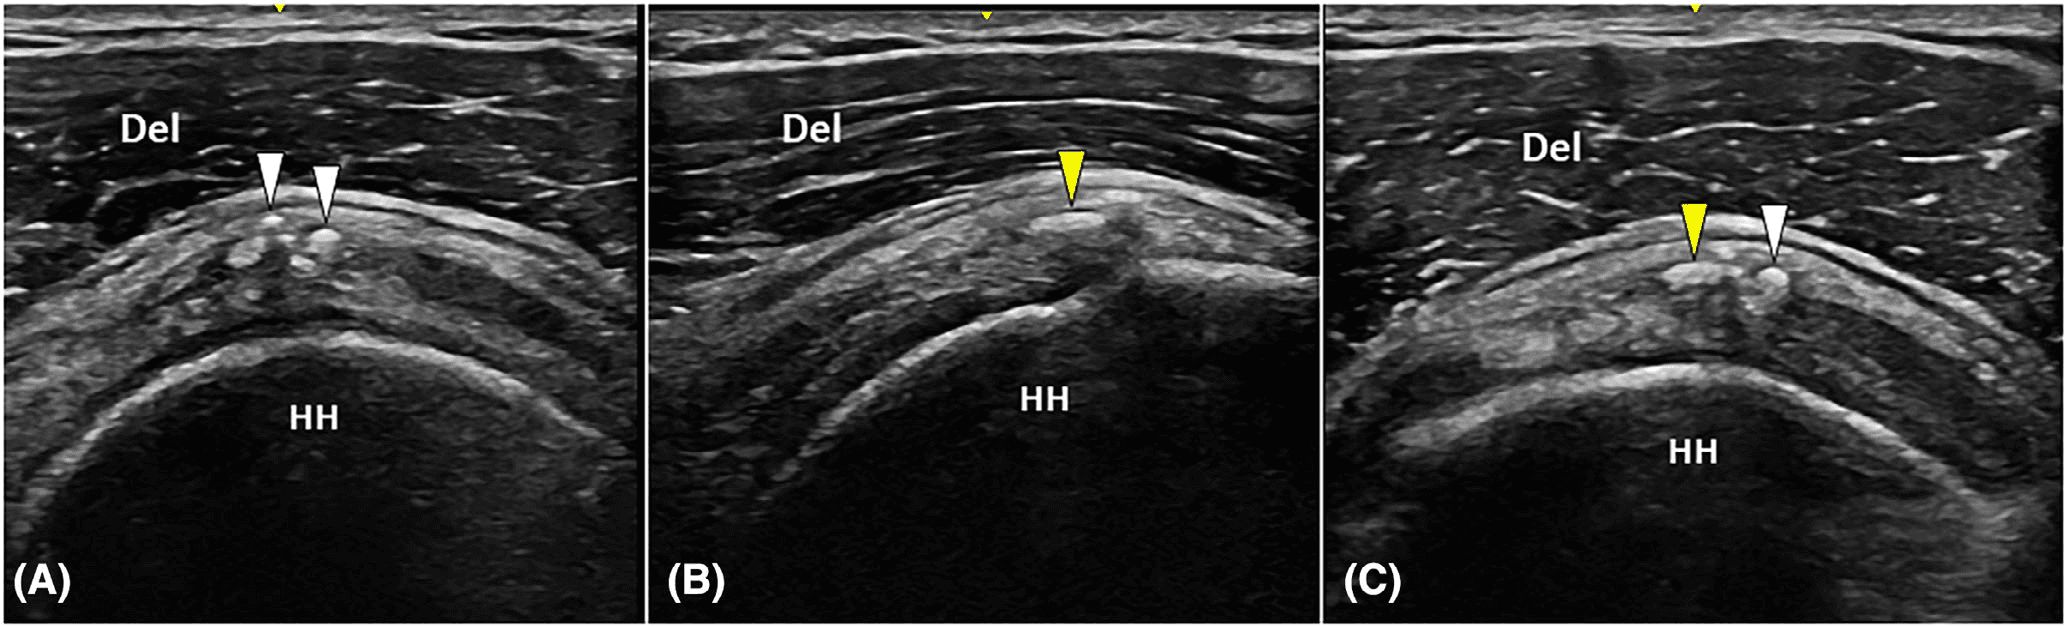

모든 환자는 치료 전 초음파 검사를 통해 관절강 내 삼출액(glenohumeral joint effusion), 견봉하-삼각근하 활액낭염(subacromial-subdeltoid bursitis), 힘줄 내 칼슘 침착물의 형태를 평가받았습니다.

치료 90일 후 결과를 분석한 결과, 견봉하-삼각근하 활액낭염이 있었던 환자군에서 모든 지표가 유의하게 나쁜 결과를 보였습니다. NRS는 6.29±2.21 vs 3.36±1.75, DASH는 44.09±8.72 vs 19.35±7.13, SPADI는 44.08% vs 27.38%로 모두 p<0.05의 통계적 유의성을 보였습니다.

관절강 내 삼출액이 있었던 환자들도 상대적으로 나쁜 결과를 보였습니다. NRS 5.40±2.15 vs 3.38±1.70, DASH 33.64±7.93 vs 23.14±6.12, SPADI 39.64% vs 33.14%였지만 통계적 유의성은 확인되지 않았습니다(p>0.05).

이번 연구 결과는 건초염 자체보다 주변 조직의 염증 상태가 체외충격파 치료 효과를 결정하는 핵심 요소임을 보여줍니다. 견봉하-삼각근하 활액낭염은 힘줄과 견봉 사이 공간의 염증으로, 충격파 에너지가 목표 부위에 효과적으로 전달되는 것을 방해할 수 있습니다.